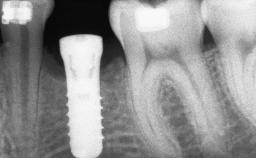

A 45-year-old woman with a completely edentulous maxilla was referred to evaluate the possibility of rehabilitation with an implant-supported prosthesis. This patient was healthy and a non-smoker. She had been wearing a maxillary complete denture opposing a natural mandibular dentition since her twenties. This situation had resulted in progressive resorption of the alveolar ridge, repeatedly creating a need for relining the denture. Twenty years later, despite multiple adaptations and the use of “glues” the denture was unstable and causing the patient psychological and functional discomfort.

# of Implants 8

Type of Implants Reduced-Diameter|Two-Piece

Bone Augmentation Horizontal|Sinus Floor Elevation|Staged|Vertical

Augmentation Materials Autogenous chips|Autogenous block(s)